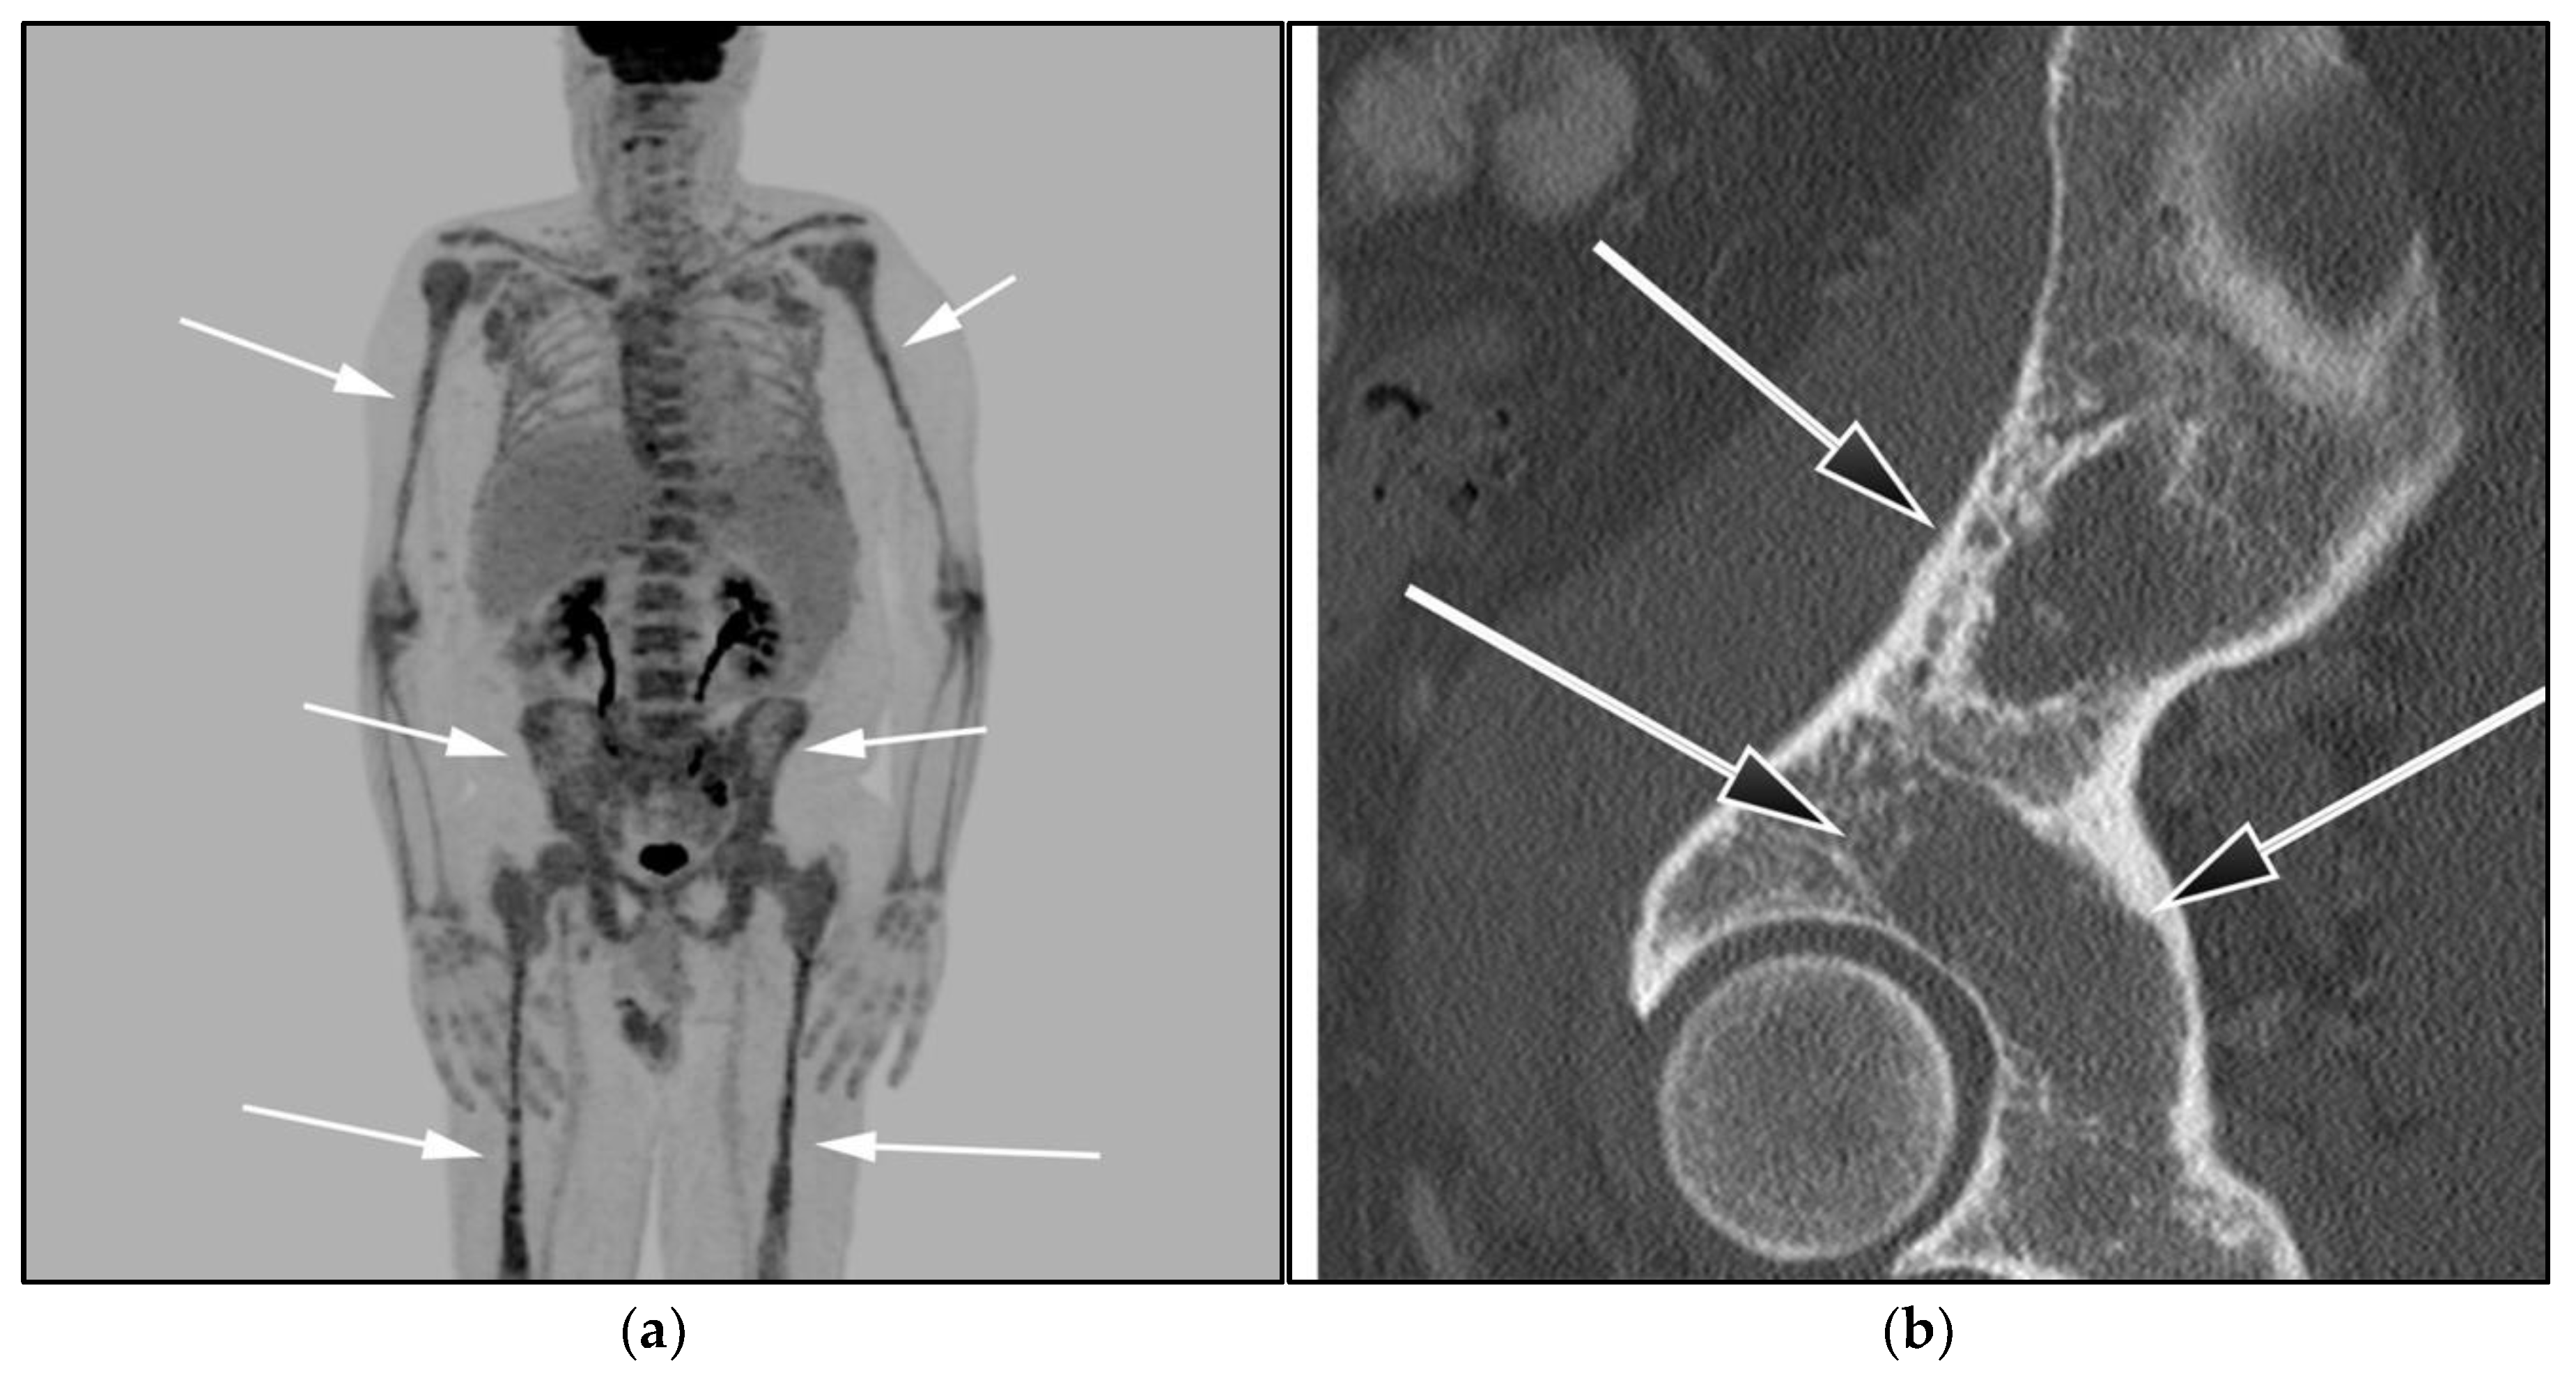

Imaging is not necessary to establish a diagnosis of ALPS but might aid in its diagnostic evaluation. Stability in the size of lymphadenopathy and hepatosplenomegaly over many years may suggest ALPS from other malignant lymphoproliferative diseases [26] (Figure 4).

Figure 4.

A 30-year-old male with known history of autoimmune lymphoproliferative disorder since childhood. (a) Maximal intensity projection (MIP) FDG PET/CT image shows generalized hypermetabolic lymphadenopathy throughout the head, neck, chest, abdomen, and pelvis (white arrows). Note that splenic activity is not visualized (thin white arrow) because the spleen was surgically removed during childhood due to splenomegaly. (b) Axial FDG PET image shows hypermetabolic adenopathy within pelvis mainly about the bilateral pelvic side wall and external iliac nodes (white arrows). Lymph nodes often show little or only modest uptake, a clue, in addition to stability of nodal size and over multiple time points. Biopsy is the only method for definitive diagnosis. (c) H&E section of a lymph node shows highly proliferative paracortical expansion composed of small proliferative lymphocytes and immunoblasts with preserved lymphoid follicular architecture. There is sinus histiocytosis. (Original magnification 400×, H&E stain).

Once the diagnosis of ALPS is established, baseline and periodic follow-up CT scans should therefore be obtained to document the stability of lymphadenopathy and hepatosplenomegaly. 18F-FDG PET/CT may also be helpful because mild to moderate FDG uptake is typical of ALPS compared to the high FDG uptake characteristic of malignant lymphomas. By evaluating for areas of high FDG uptake, 18F-FDG PET/CT may help in the early detection of lymphoma transformation and demonstrate the best site for biopsy, when indicated [23]. Awareness of ALPS is pivotal because ALPS often requires long-term immunosuppressive therapies as opposed to chemotherapy that is standard for malignant lymphoproliferative disorders.